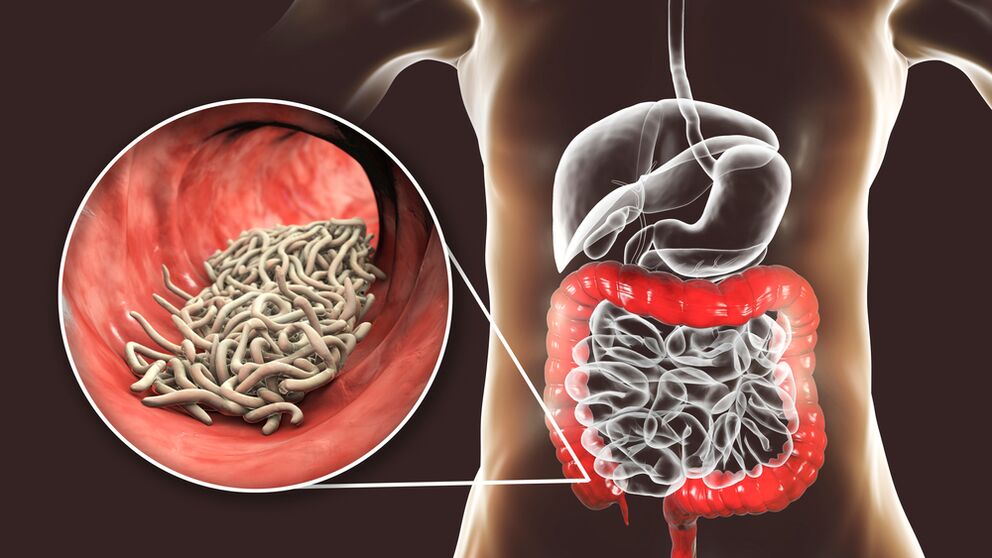

Resultados de ensayos clínicos

Numerosos estudios han confirmado la eficacia NEOflorax:

| Indicador |

Resultado |

| Eliminación de parásitos |

El 95% de los pacientes notaron una disminución en la cantidad de helmintos. |

| Normalización del tracto gastrointestinal. |

El 89% de los sujetos informaron una mejor digestión. |

| Restauración de la microflora. |

El 92% de los participantes notaron una disminución de los síntomas de disbiosis. |

| salud general |

El 90% de los encuestados notó un aumento en la calidad de vida. |